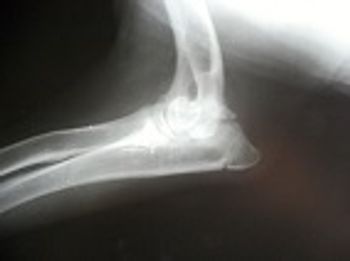

In a recent study, investigators conducted bone density (BD) analysis of healthy and diseased elbow joints in Labrador retrievers and Golden retrievers.